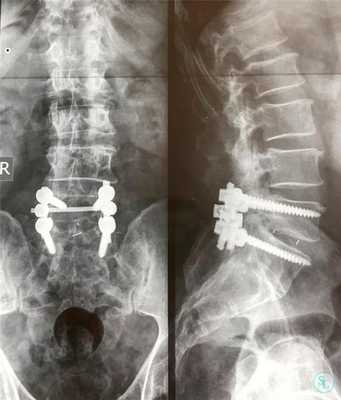

Техника декомпрессивной операции

Сразу отметим, что такой хирургический подход определенным образом чреват дестабилизацией ламинэктомированных костных тел. Поэтому довольно часто возникает необходимость в проведении ламинэктомии с фиксацией позвонков, то есть совместно со спондилодезом. А это означает, что по завершении основного процесса хирургии пара или несколько позвонков могут быть скреплены между собой специальной металлической пластиной, возможно, дополнительно понадобится произвести трансплантацию костной ткани, взятой у пациента из подвздовшной кости. Благодаря произведенной фиксации соединенные элементы хоть и будут обездвижены, каких-либо существенных ограничений подвижности люди, как правило, не испытывают.

Сращение позвонков на рентгене.

Стабилизирующие конструкции

Удаление тел, их отростков и других анатомических структур чревато дестабилизацией подвергшегося вмешательству позвоночно-двигательного сегмента, а также повышению риска развития тяжелых прогрессирующих кифотических и сколиотических деформаций. Причем чаще страдает поясничный и шейный отдел, а также в переходные зоны.

Это обуславливает необходимость часто использовать на завершающем этапе операции методики фиксации позвонков. Особенно они важны при выполнении ламинэктомии у детей и подростков, поскольку в таких случаях ситуация усугубляется асимметричным ростом позвонков.

Одним из способов стабилизации прооперированного позвоночно-двигательного сегмента является спондилодез. Его выполнение подразумевает установку специальных опорно-стабилизирующих конструкций, прочно соединяющих соседние позвонки в области воздействия между собой. В определенных случаях дополнительно требуется провести трансплантацию взятого у пациента из подвздошной кости фрагмента. В результате позвонки плотно срастаются между собой и теряют способность двигаться. Но при проведении ламинэктомии на 1 или 2 позвонках и их спондилодезе пациенты обычно не замечают существенных ограничений при движениях.